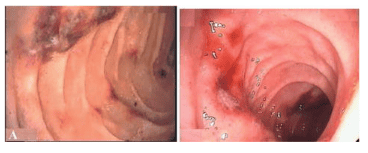

Nội soi dạ dày-tá tràng ở bệnh nhân có ban xuất huyết Henoch-Schonlein

Ở những bệnh nhân này có các triệu chứng bụng rõ ràng, nội soi được coi là một công cụ hữu ích để xác định chẩn đoán và loại trừ các trường hợp cấp cứu ngoại khoa khác. Người ta báo cáo rằng tá tràng là vị trí tổn thương phổ biến nhất, các vị trí khác như dạ dày, thân vị và các góc bờ cong, nhưng không bao giờ là tâm vị hoặc thực quản. Các phát hiện qua nội soi bao gồm sung huyết, phù nề, chấm xuất huyết, loét và các tổn thương nội mạc khác bao gồm các phát hiện nội soi thường gặp của ban xuất huyết Henoch-Schonlein. Những biểu hiện này ít nhiều trùng lặp với những biểu hiện nhiễm H. pylori, do đó việc phát hiện vi khuẩn là rất quan trọng trong việc điều trị một số bệnh nhân.

Hình ảnh nội soi ban xuất huyết Henoch-Schonlein ở tá tràng